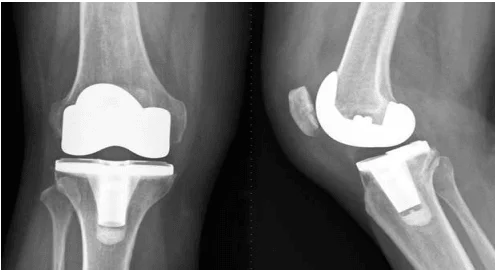

Knee Replacement

A total knee replacement is a surgical procedure whereby the diseased knee joint is replaced with artificial material. The knee is a hinge joint which provides motion at the point where the thigh meets the lower leg. During a total knee replacement, the end of the thigh bone (femur) is removed and replaced with a metal shell. The end of the lower leg bone (tibia) is also removed and replaced with a channeled plastic piece with a metal stem. Depending on the condition of the kneecap portion of the knee joint, a plastic “button” may also be added under the kneecap surface. The artificial components of a total knee replacement are referred to as the prosthesis.